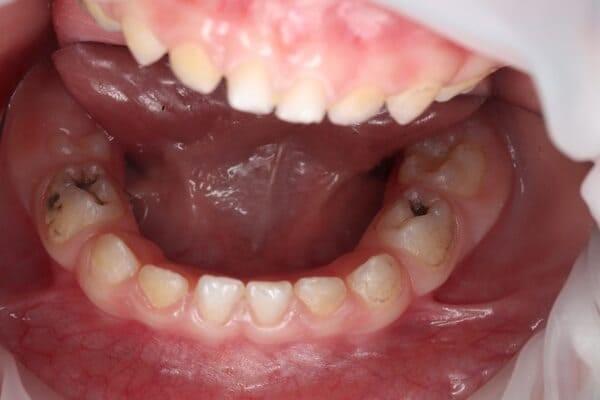

Один рік і два місяці вік дитини. Хтось скаже: «Що там тим зубам можна лікувати?!» Однак є ситуації, коли каріозний процес розвивається просто блискавично. Часто це пов’язано з порушеннями у формуванні твердих тканин ще внутрішньоутробно. А коли такі зубчики прорізуються, руйнування відбувається просто «на очах». Вісім із восьми зубів уражені, а 4 з них потребують часткового видалення пульпи («нерва»). На цьому етапі зуби вже починають турбувати і не зважаючи на юний вік дитини, зволікати не можна. Завдяки високій компетенції наших анестезіологів, які працюють з дітьми від самого народження і навіть з передчасно народженими, ми можемо проводити відповідне лікування в анестезіологічному забезпеченні за потреби навіть з першого зуба. Верхнім зубчикам, які сильно уражені, служити до 7-8 років, тому вони покриваються стандартними естетичними цирконієвими коронками, які дають максимальний результат по надійності, функції та естетиці. Година з половиною роботи і дитина може знову кусати без болю і дискомфорту. Важливо пам’ятати: для лікування зубів ніколи не буває “зарано”, це потрібно робити тоді, коли є відповідні показання